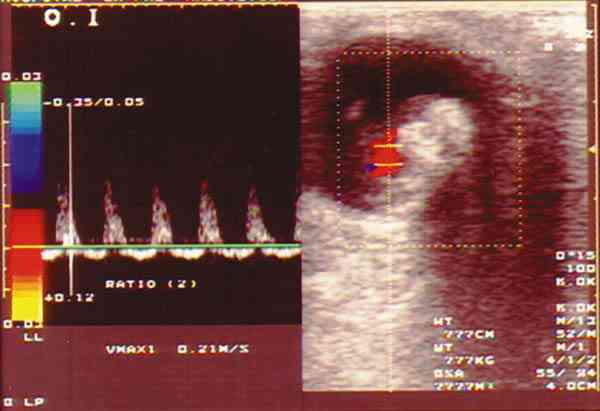

Figura 3. Retinoblastoma vascularizado mediante el doppler color se

observa el registro correspondiente a un vaso arterial.